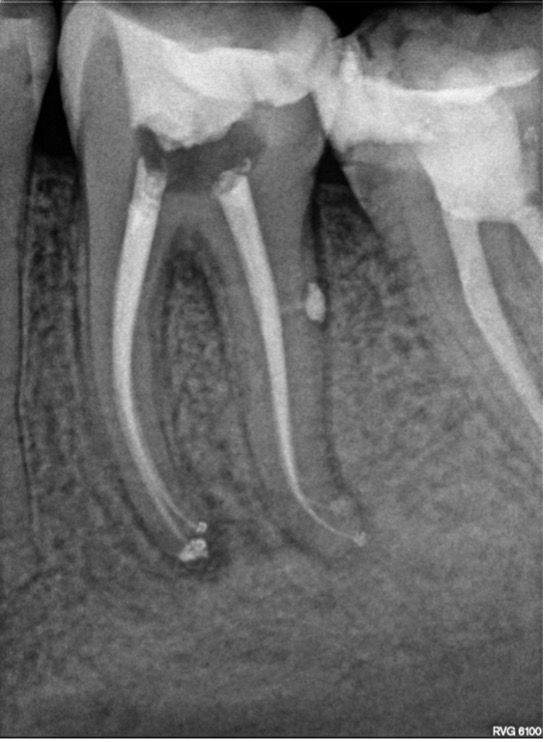

Biopulpectomía en pulpitis irreversible utilizando BlueShaper®, Z-Glider, Fast Pack y Fast Fill

Caso de pulpitis irreversible tratada con los sistemas de instrumentación BlueShaper® y limas Z-Glider ambas de Zarc por el doctor José Conde en su clínica de endodoncia exclusiva, Clínica Conde País.